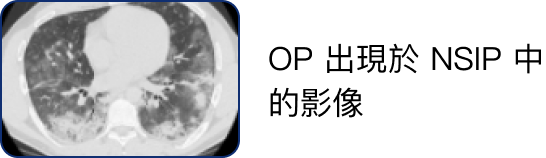

高解析電腦斷層掃描 (HRCT)3

自體免疫疾病相關的肺纖維化病人 HRCT 檢查結果中,最常出現非特異性間質性肺病 (NSIP) 及尋常性間質性肺病 (UIP) 的影像,較少出現器質性肺炎 (OP) 的影像。

• 硬皮症病人的影像結果較常出現 NSIP,而 UIP 則可見於 40% 的硬皮症病人。

• 多發性肌炎及皮肌炎病人的影像結果較常出現 NSIP 與 OP 的重疊影像。